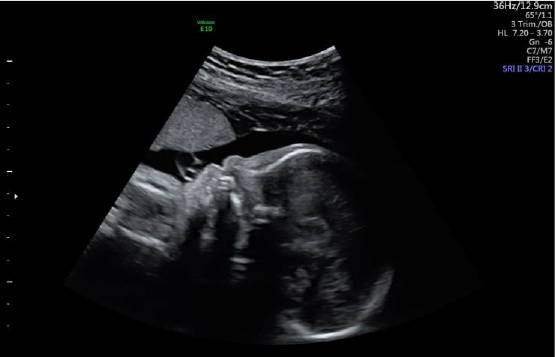

A 30-year-old woman with normal family history, gravida 2, para 1, underwent a sonographic examination at 29 weeks of pregnancy for the first time at Vinmec Times City International Hospital (Hanoi, Vietnam). Historically, the 12th week ultrasound examination showed no sign of abnormality (NT 2.3mm), and the patient did not take the double test. The triple test showed low risk for chromosomal aneuploidy. At 29th week, the ultrasound analysis revealed the fetal features including complete atrioventricular septal defect (Figure 1) but normal great vessel courses; absent nasal bone (Figure 2); facial profile of DS; bilateral brachy mesophalangia of the fifth digit; a short femur (51mm - 5.6 percentile) and humerus (43mm - <1 percentile) for gestational age (29 weeks and 4 days). The clinical doctor indicated invasive tests including quantitative fluorescence PCR (QF-PCR) and cytogenetic analysis (karyotyping) from amniotic fluid. QF-PCR was performed using Devyser Compact v3 kit (DevyserAB, Sweden). The results were described according to the International System for Human Cytogenetic Nomenclature (ISCN 2016).

We reported here a prenatal case with the finding of complete atrioventricular septal defect (AVSD), absent nasal bone, facial profile of DS, bilateral brachy mesophalangia of the fifth digit, a short femur and humerus for gestational age. The positive likelihood ratio of nasal bone absence for DS screening was estimated around 29.00-66.75 [7]. This abnormality is commonly used as soft markers to screen for DS during the first or second trimester ultrasound. Du et al. [7] described 38 cases of DS among the 56 707 singleton pregnancies suggested that the sensitivity and specificity of the absent fetal nasal bone marker in detecting DS were 31.58 and 99.90%, respectively. The positive and negative predictive values were 16.90 and 99.95%, respectively [7]. In the study of Vos, et al. [8], they described two new methods for assessing the relationship between the mandible and maxilla: the maxilla-nasal-mandible (MNM) angle and the fetal profile (FP) line. The MNM angle, defined as the angle between the maxilla-nasal and mandible-nasal lines, is constant throughout pregnancy at about 13.5° in euploid fetuses, whereas the angle was much smaller (8.2°-11.2°) in the fetuses with DS. The fetus in our study has the MNM angle of 11°.